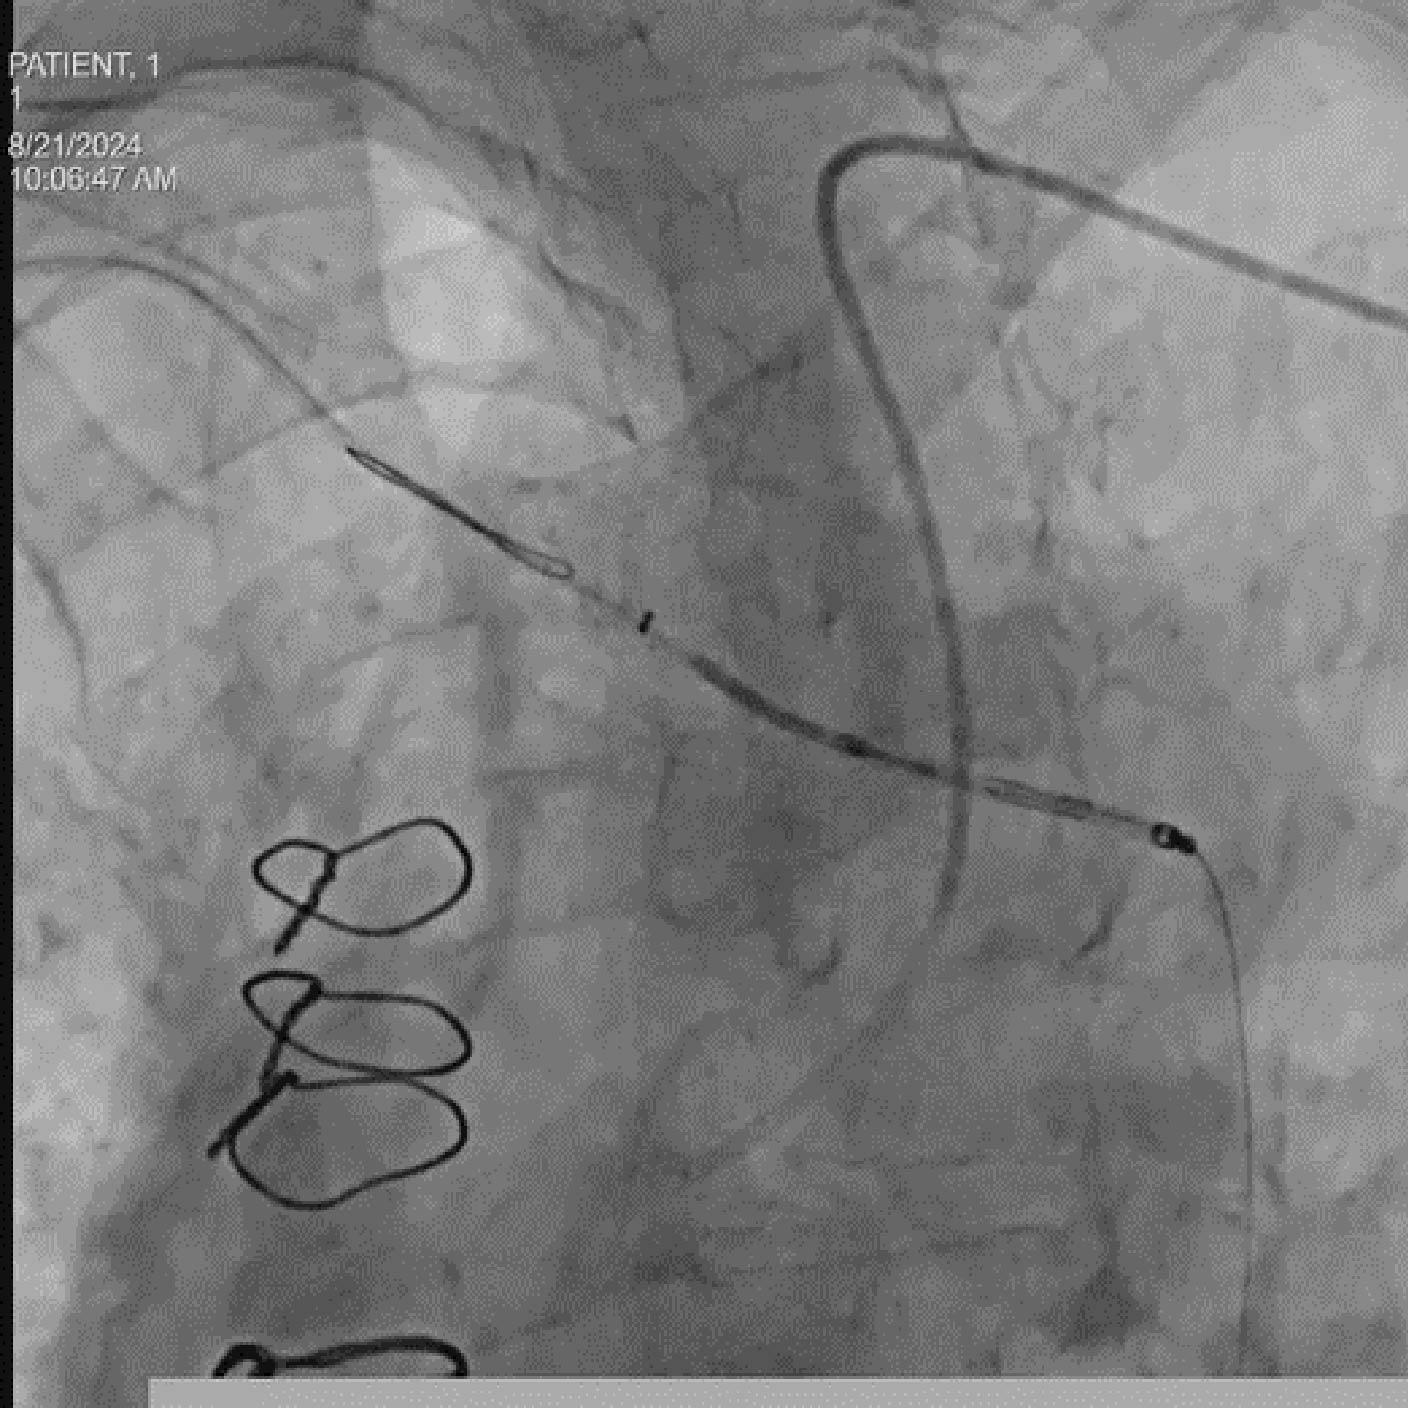

- Colocación del guía y del dispositivo con syngo Aortic Valve Guidance

- Despliegue del dispositivo SAPIEN 3

Soluciones y características seleccionadas: ARTIS pheno, Case Flows, Una combinación preestablecida de configuraciones (angulación, disposición de la pantalla, etc.), personalizada para la colocación del dispositivo SENTINEL™*, reduce las interacciones con el sistema. Con Case Flows, una única interacción del usuario reemplaza el ajuste de hasta 6 configuraciones del sistema³. syngo 2D/3D Fusion - Aplicación para superponer la anatomía de la arco aórtico basada en tomografía computarizada sobre fluoroscopia en vivo, para apoyar la navegación del dispositivo. Se ha demostrado que la guía por fusión reduce significativamente el tiempo de despliegue del dispositivo SENTINEL™* y el uso de contraste⁴.

Soluciones y características seleccionadas: 3mensio (Pie Medical Imaging) Software semiautomatizado para asistir en la reconstrucción 3D de la válvula previamente implantada y la anatomía circundante, con el fin de determinar el abordaje ideal y el tamaño adecuado de la válvula. Su uso reduce el tiempo de planificación del TAVR¹ y los resultados de la planificación pueden exportarse para superposición en tiempo real durante la fluoroscopia.